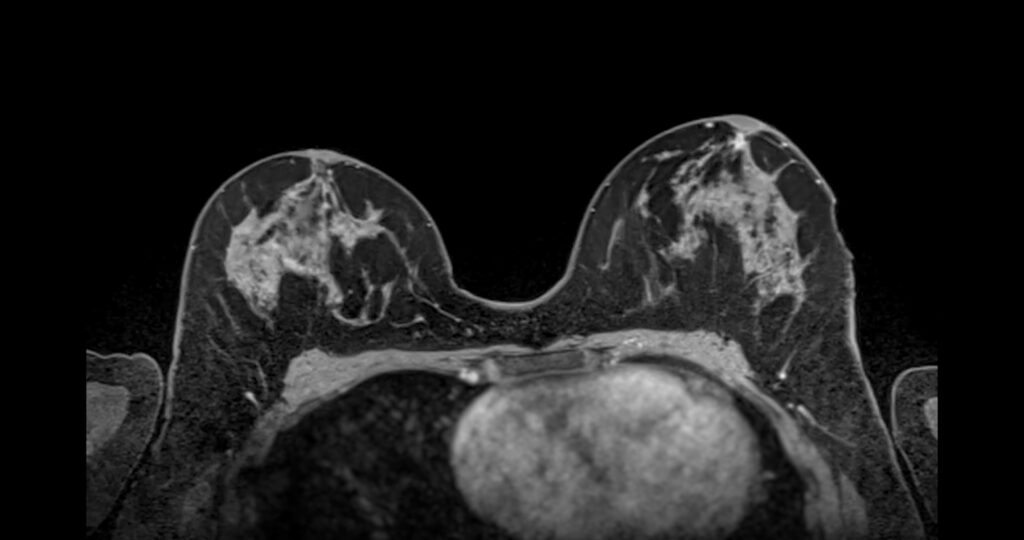

Breast MRI

Breast MRI (magnetic resonance imaging) is one of the most sensitive imaging methods available for detecting breast cancer.

MRI uses powerful magnets and radio waves to create detailed images of breast tissue. A contrast agent is typically used to highlight areas with increased blood flow, which may indicate abnormal tissue.

Breast MRI is generally recommended forpatients at higher risk of breast cancer, including those with strong family histories or known genetic mutations. According to the National Comprehensive Cancer Network, MRI screening may be used alongside mammography for individuals with elevated risk factors.